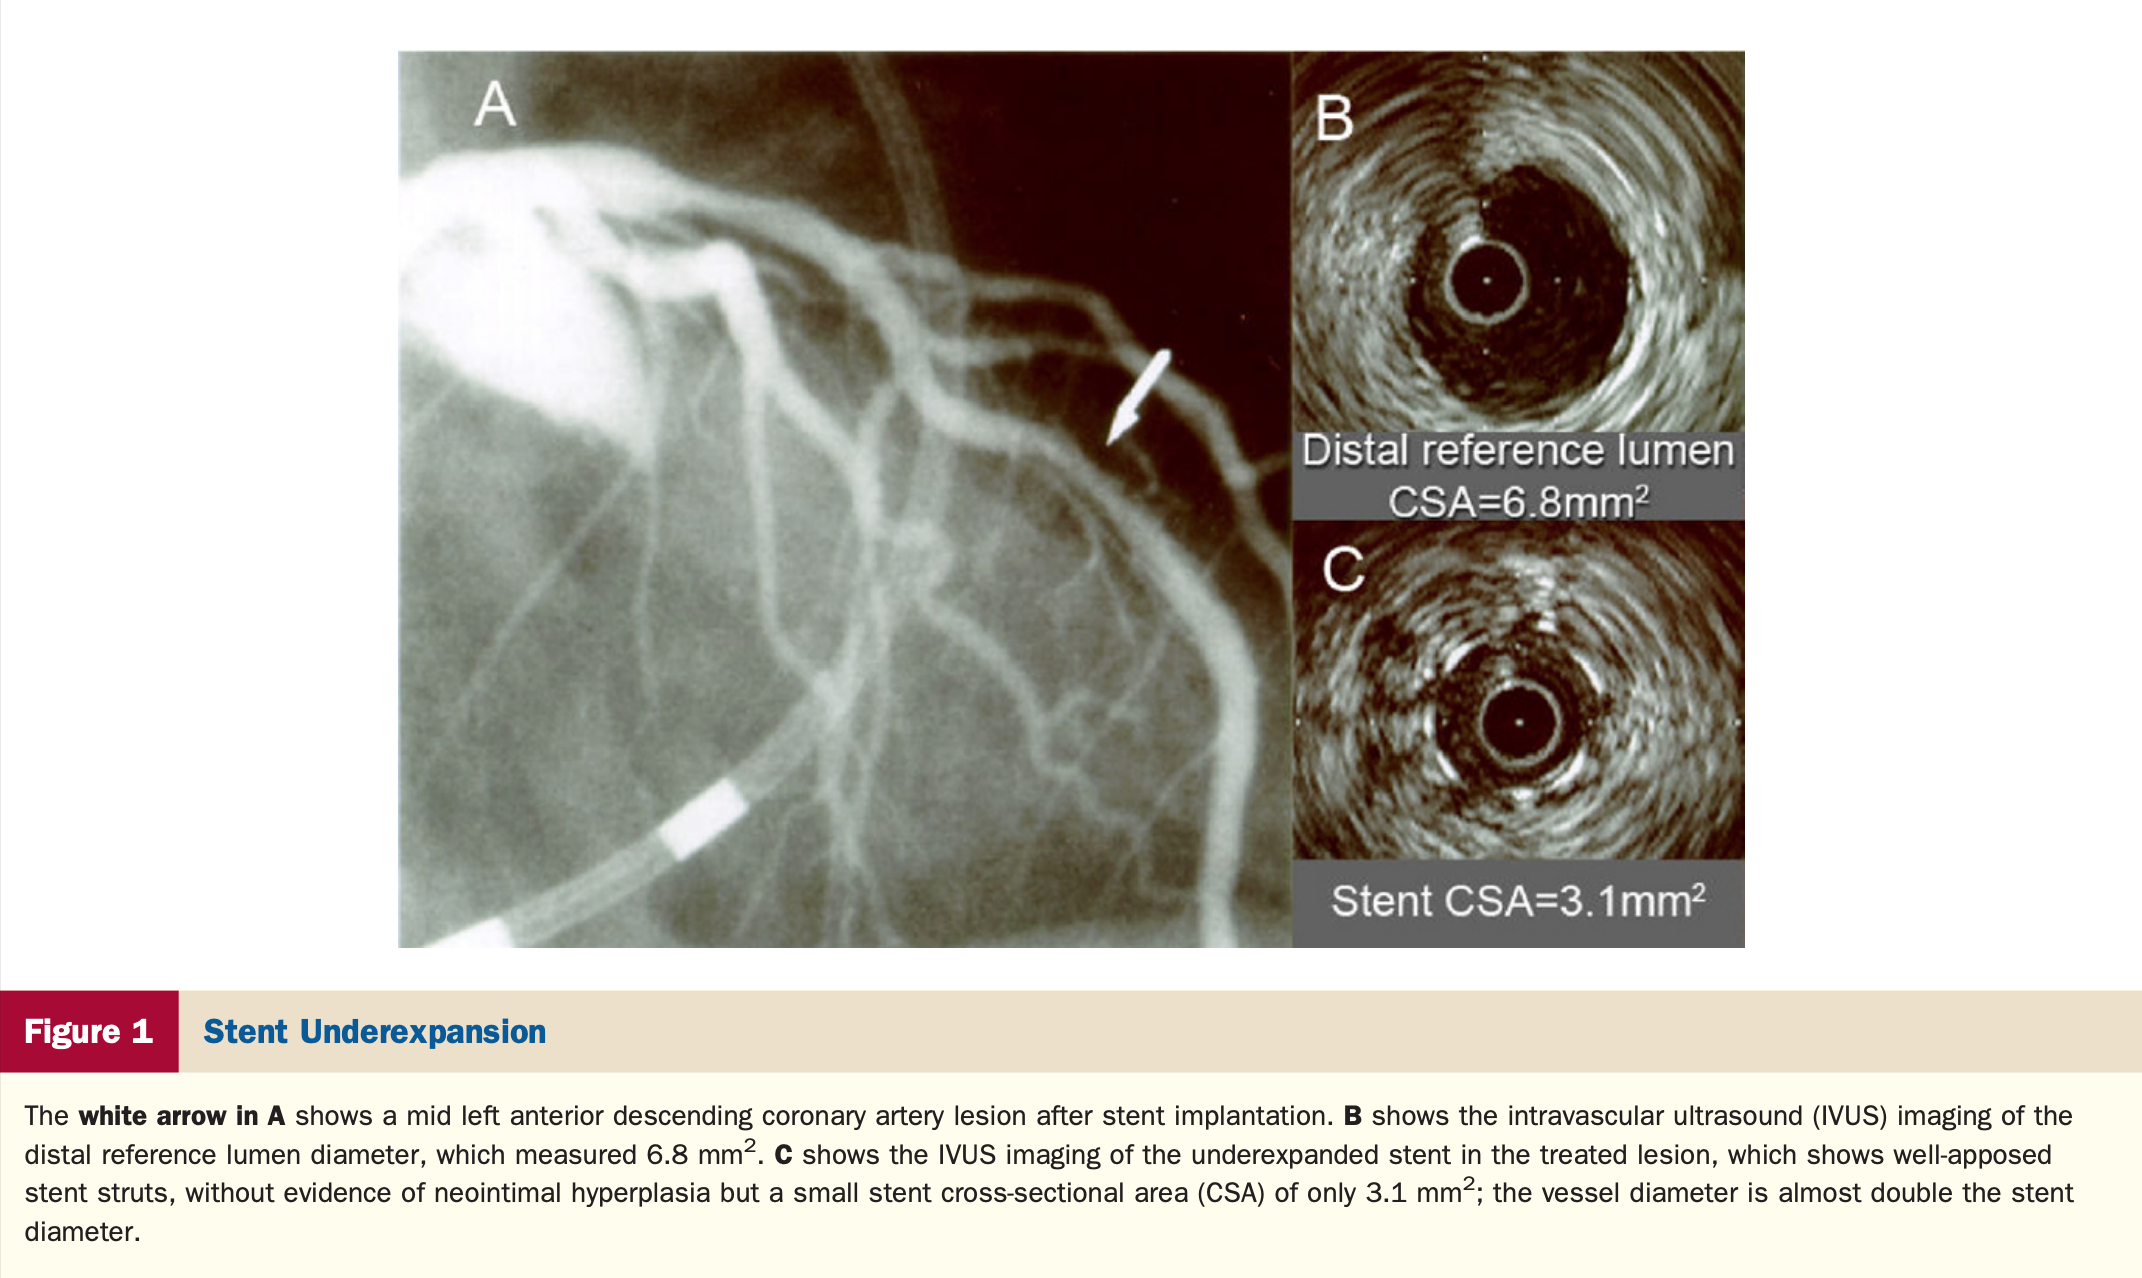

In patients with stent failure, IVUS or OCT is reasonable to determine the mechanism of stent failure (Class IIa).

• "Assessment  of  the  cause  of  stent  thrombosis  with  intracoronary  imaging  is  important to guide subsequent treatment. Similarly, advanced  imaging  techniques  have  an  important  role in detecting underlying mechanical and pathophysiological  factors  that  contribute  to  in-stent  restenosis  (ISR),  such  as  neointimal  hyperplasia,  stent  underexpansion,  and  fractures."

Stent Failure

Stent Underexpansion

https://www.jacc.org/doi/abs/10.1016/j.jacc.2010.07.028